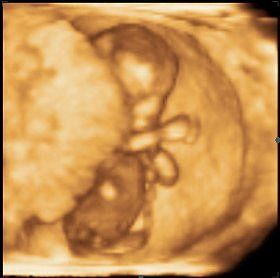

И вот фото гипертонуса по узи, и как это выглядит на самом деле. Покажите ольге белокурой.

Лер, у меня матка 55х33х18, это банан по форме, не есть хорошо. А должен быть апельсин.